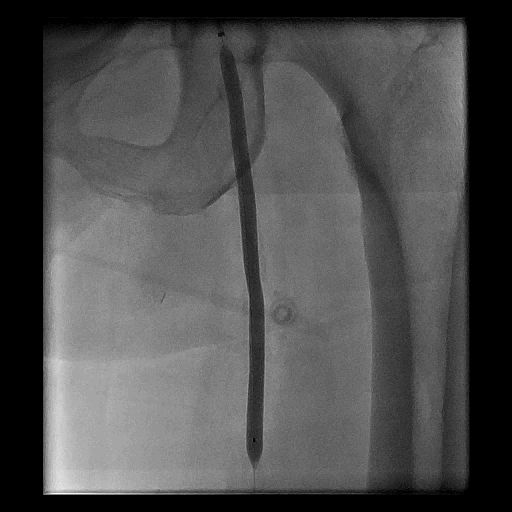

Figure 1. 淺股動脈的使用經皮腔內血管成形術治療

B. 氣球擴張術治療